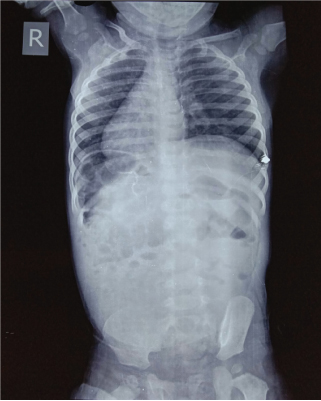

Plain chest and abdominal X-ray showed dextrocardia with higher level of left hemi diaphragm with gastric fundal air on right side (Fig. 1). Two-dimensional echocardiography showed situs inversus, dextrocardia with normal ventricular function with no other cardiac anomaly. Ultrasonography (USG) of abdomen revealed liver on left side with situs inversus and bilobed spleen on right side. Due to obscured gases pancreas was not clearly visualized. The proximal part of superior mesenteric artery and superior mesenteric vein were visualized on color Doppler. USG abdomen of both parents showed situs solitus. Upper gastro intestinal contrast was study done with non-ionic contrast which revealed gastro-esophageal junction and gastric fundus was located on right side of spine with pylorus, duodenum located on left side of spine with grossly distended stomach. Delayed images revealed slow opacification of small bowel (after 2 hours), suggestive of partial duodenal obstruction (Fig. 2). Routine blood investigations, liver and renal function test were within normal limits.

Fig. 1

Plain X-ray of situs inversus.